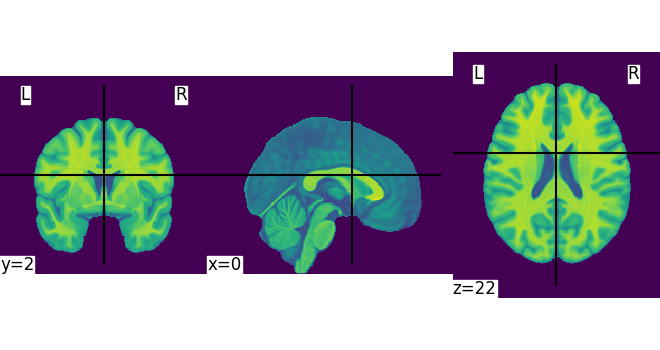

Let’s quickly plot this file:

from nilearn import plotting

plotting.plot_img(MNI152_FILE_PATH)

<nilearn.plotting.displays._slicers.OrthoSlicer object at 0x7f3bb4d72ab0>

This is not a very pretty plot. We just used the simplest possible code. There is a whole section of the documentation on making prettier code.